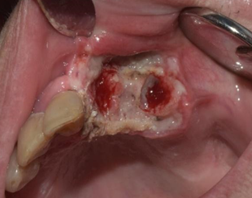

Se solicita a la paciente que concurra a la próxima consulta con informe histopatológico de la nefrectomía realizada y coordinar para la semana siguiente la biopsia incisional de la lesión oral. En esta segunda consulta, clínicamente se constata en la lesión un aumento de volumen considerable (Figs. 4 y 5). El resultado histopatológico de la nefrectomía realizada fue de carcinoma renal de células claras.

A causa de la velocidad de crecimiento constatada en una semana y el diagnóstico de la lesión renal previa, se plantea, previo a la biopsia, un diagnóstico presuntivo de metástasis renal.

Evolución de la lesión a la semana de ser evaluado, en la segunda consulta

Durante el procedimiento de la biopsia incisional, se decide realizar cambio de táctica a exéresis de toda la lesión clínicamente visible, con el objetivo de controlar la hemorragia intraoperatoria y conseguir una correcta hemostasis. Se realizan además las exodoncias de las piezas 2.1 y 2.3 con el mismo fin. (Figs. 6 y 7)